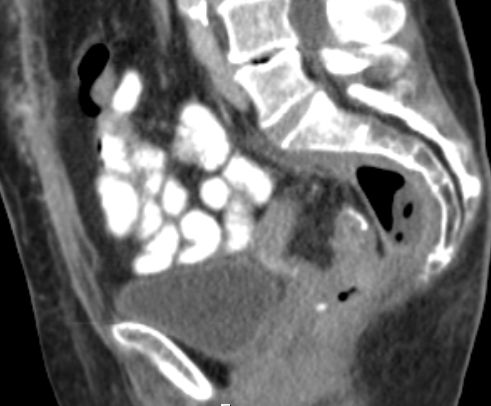

praesakraler Abszess 81-jährige Frau mit Rektumkarzinom uT3 uNo vor 2 Monaten . Praeoperative Bestrahlung mit 5x5Gy, tiefe anteriore Rektumextirpation mit protektivem Ileostoma. Jetzt Relaparotomie, Abszessdrainage.